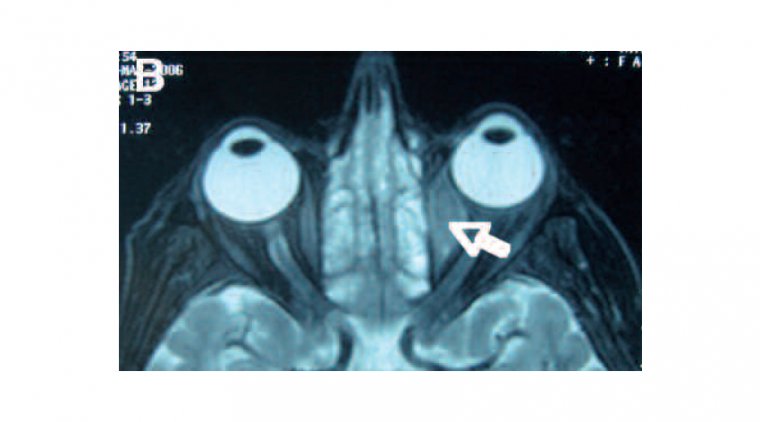

Orbital lymphoma is a type of cancer that affects the lymphatic system, specifically the tissues in and around the eye socket (orbit). It is a rare form of lymphoma, accounting for only 1-2% of all cases. Orbital lymphoma can affect people of any age, but it is more common in older adults and individuals with compromised immune systems.